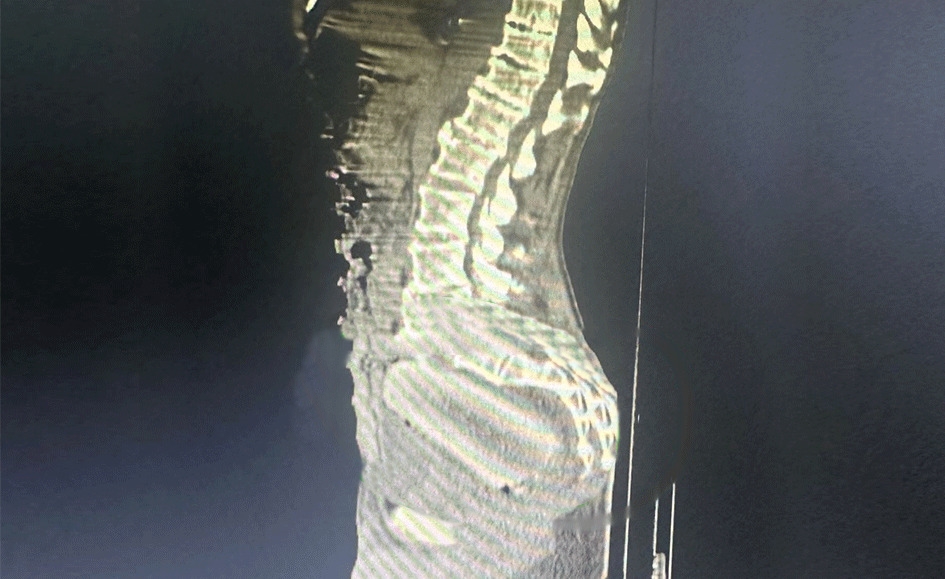

An image from an X-ray showed it was wedged deep inside the man’s rectum.